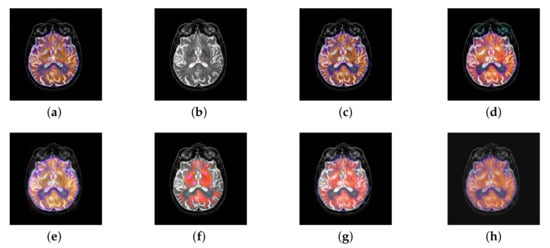

In this section, all FDG images are derived from the normal human brain, but the angle is chosen differently in Figure 24. In Figure 25, Figure 26, Figure 27 and Figure 28, we find that the color information obtained by the image fusion method based on NSCT, DTCWT, and LPSR is better preserved, but the structure information is lost more. The fusion image based on GFF, IGM, and FusionCNN method retains the complete structure information in the MRI image, but the color obtained from the FDG image is distorted. The image color information obtained by DDcGAN fusion method is too bright, resulting in unclear color area details and low contrast of color region. In contrast, the image obtained by our algorithm has moderate brightness of color information, complete structure information, and complete biological detail information.

Figure 25.

Fused medical images obtained by different algorithms (Figure 24a,b): (a) DTCWT, (b) GFF, (c) NSCT, (d) LPSR, (e) IGM, (f) FusionCNN, (g) DDcGAN, and (h) FusionNet.

Figure 26.

Fused medical images obtained by different algorithms (Figure 24c,d): (a) DTCWT, (b) GFF, (c) NSCT, (d) LPSR, (e) IGM, (f) FusionCNN, (g) DDcGAN, and (h) FusionNet.

Figure 27.

Fused medical images obtained by different algorithms (Figure 24e,f): (a) DTCWT, (b) GFF, (c) NSCT, (d) LPSR, (e) IGM, (f) FusionCNN, (g) DDcGAN, and (h) FusionNet.

Figure 28.

Fused medical images obtained by different algorithms (Figure 24g,h): (a) DTCWT, (b) GFF, (c) NSCT, (d) LPSR, (e) IGM, (f) FusionCNN, (g) DDcGAN, and (h) FusionNet.